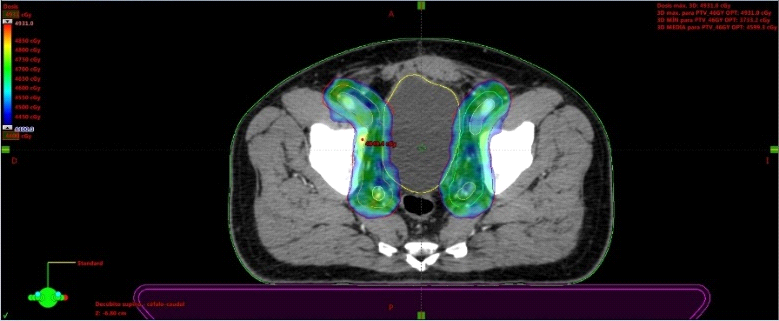

Fig. 2. Técnica de IMRT (Radioterapia de intensidad modulada). Se observa como la conformación de la dosis terapéutica protege de manera segura los órganos de riesgo (OARS). La zona de color, muestra la dosis de radiación terapéutica (46Gy) sobre las regiones ganglionares a nivel ilíaco interno, externo y obturatriz. Se evidencia así que las dosis llegan exclusivamente a la zona de interés, respetando la vejiga y el recto.

Fig. 2b. Técnica de IMRT (Radioterapia de intensidad modulada). La zona de color, muestra la dosis de radiación terapéutica (70Gy) sobre la próstata. Se evidencia que la dosis alta sólo llega sobre el target, respetando hacia posterior el recto.